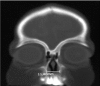

Introduction: Nasal obstruction is an important condition that can lead to severe respiratory distress in newborns. There are several differential diagnoses, and one of them is congenital nasal pyriform aperture stenosis (CNPAS). CNPAS is a rare case of respiratory distress caused by excessive growth of the nasal process of the maxilla and leads to narrowing of the anterior third of the nasal cavity. Diagnosis, associated anomalies, and treatment strategies are reviewed by the following presentation of two cases.

Case presentation: We report two cases of infants diagnosed with CNPAS. The patients in the first case had no concomitant comorbidities, and the outcome was successful after surgical correction of stenosis. The patient in the second case had an associated holoprosencephaly, and although surgical correction and nasal cavity patency, the patient remains dependent on tracheostomy due to dysphagia and neurologic impairment.

Discussion: Airway obstruction affects 1 in 5000 children, and CNPAS is a diagnosis frequently forgotten and even unknown to neonatal and pediatric intensivists. Newborns are obligate nasal breathers, and, nasal obstruction, therefore, can lead to severe respiratory distress. CNPAS is not only rare but, many times, is not easily recognized. It is important to bear in mind the diagnostic criteria when evaluating infants with nasal obstruction. Conservative treatment should be prioritized, but surgical treatment is required in severe cases with failure to thrive and persistent respiratory distress. Respiratory distress and dysphagia may persist to some degree despite correction of the stenotic pyriform aperture due to associated narrowing of the entire nasal cavity and association with other anomalies. Final Comments: CNPAS is a rare condition and may be lethal in newborns. Differential diagnosis of nasal obstruction must be remembered to recognize this anomaly, and the otolaryngologist must be familiarized with this condition and its diagnosis. Precise surgical treatment in severe cases have high rates of success in children without other comorbidities.